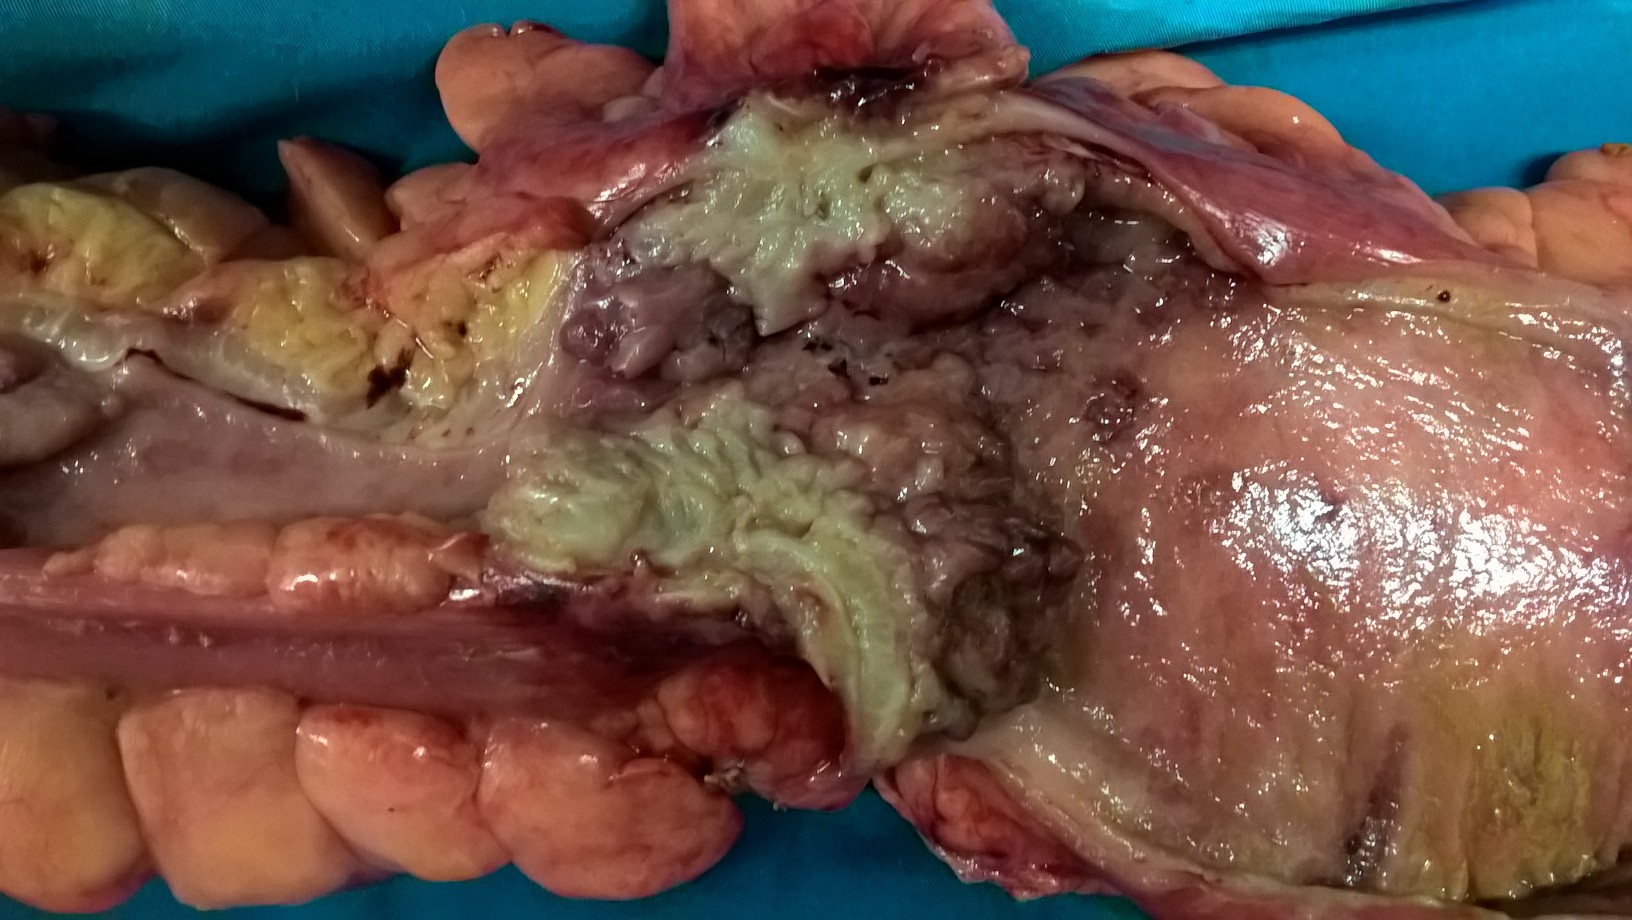

Εκτεταμένη κολεκτομή ισχαιμικού νεκρωτικού παχέος εντέρου (Ευγενική παραχώρηση Dr. V. Penopoulos)